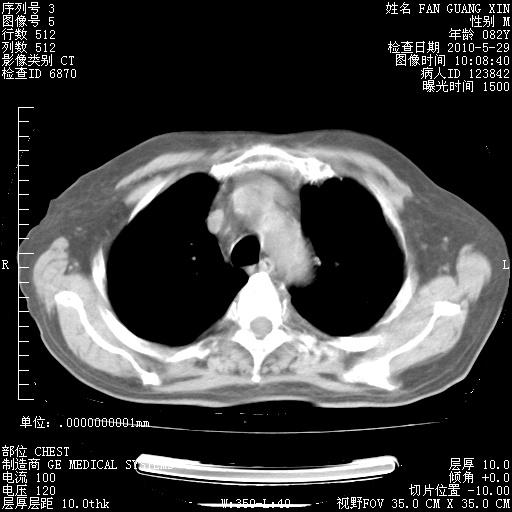

治疗3周后的肺部CT纵隔窗

再治疗10天后的肺部CT